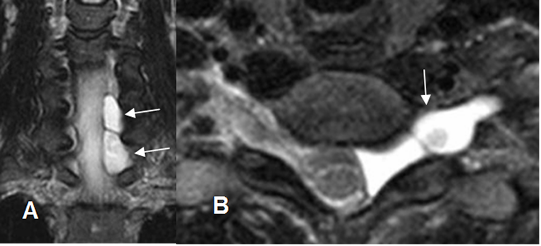

Fig 226. Quiste radicular.

A: RM sagital y B: RM axial en T2. Imagen redondeada y de consistencia líquida, a nivel paramediano derecho, que comprime las raíces.

Fig 227. Quiste radicular.

A: RM sagital en T1 y B: RM axial en T2. Lesión ovalada y de consistencia líquida, que ocupa el canal medular a nivel del sacro.